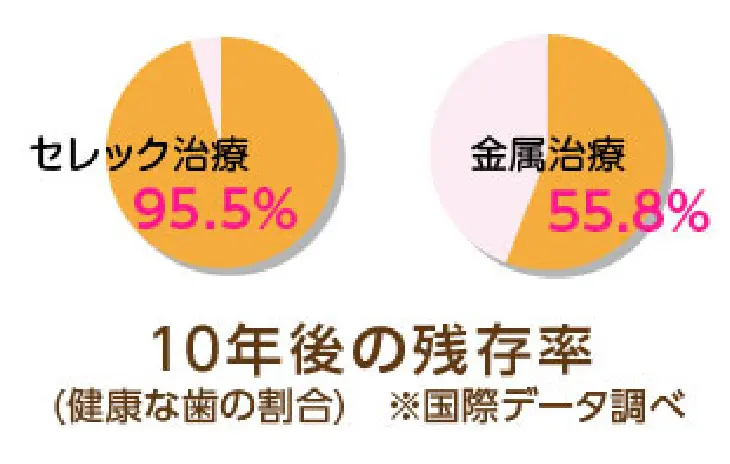

再治療を防げるのはセラミックだけ

10年後もあなたの歯を守るために

当院では、歯を長持ちさせるため、

歯と一体化し強度の高さと審美性の高さを兼ね備えた

「セラミック」と呼ばれる素材を使用して治療を行うため、